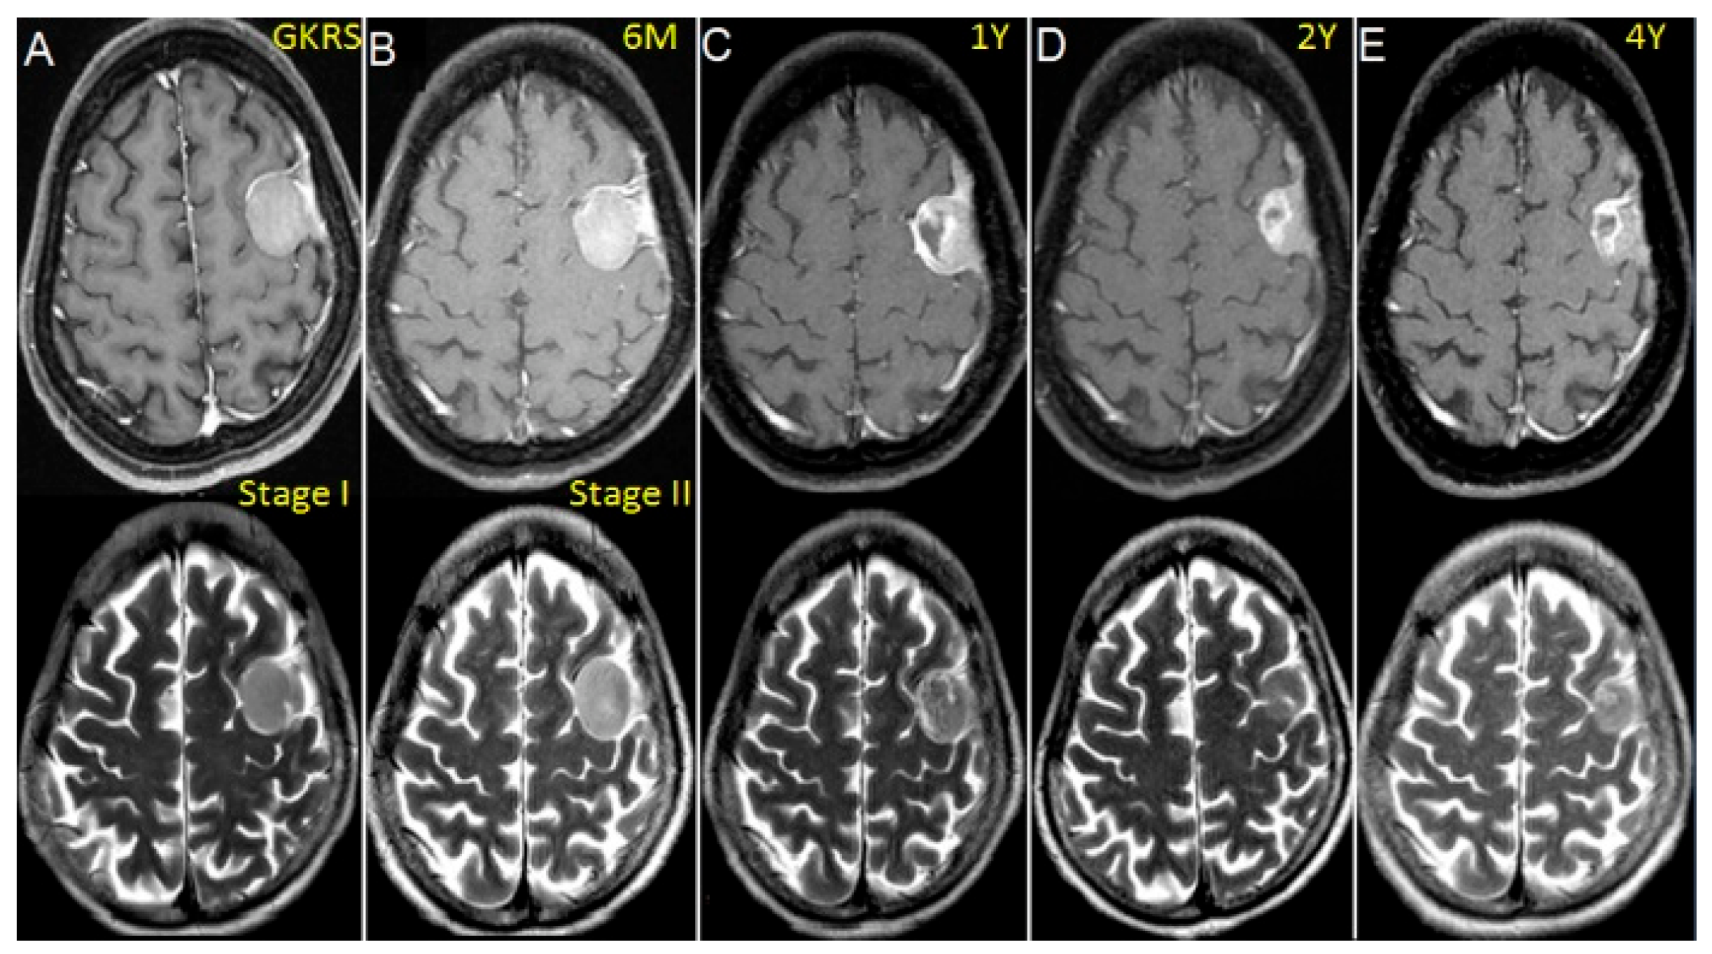

2.2. Treatment Approach and Exposure Variable

3.2. Outcome